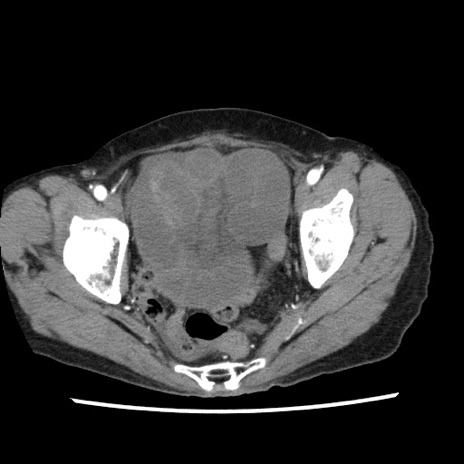

【症例】80歳代女性

【主訴】腹痛

【現病歴】8時間前から腹痛あり来院。

【既往歴】糖尿病、脂質異常症、子宮体癌にて子宮全摘術

【身体所見】意識清明・会話良好だが腹痛で苦悶様、全腹部にわたって反跳痛と圧痛あり

【データ】WBC 13600、CRP 0.14、LDH 224、CK 90